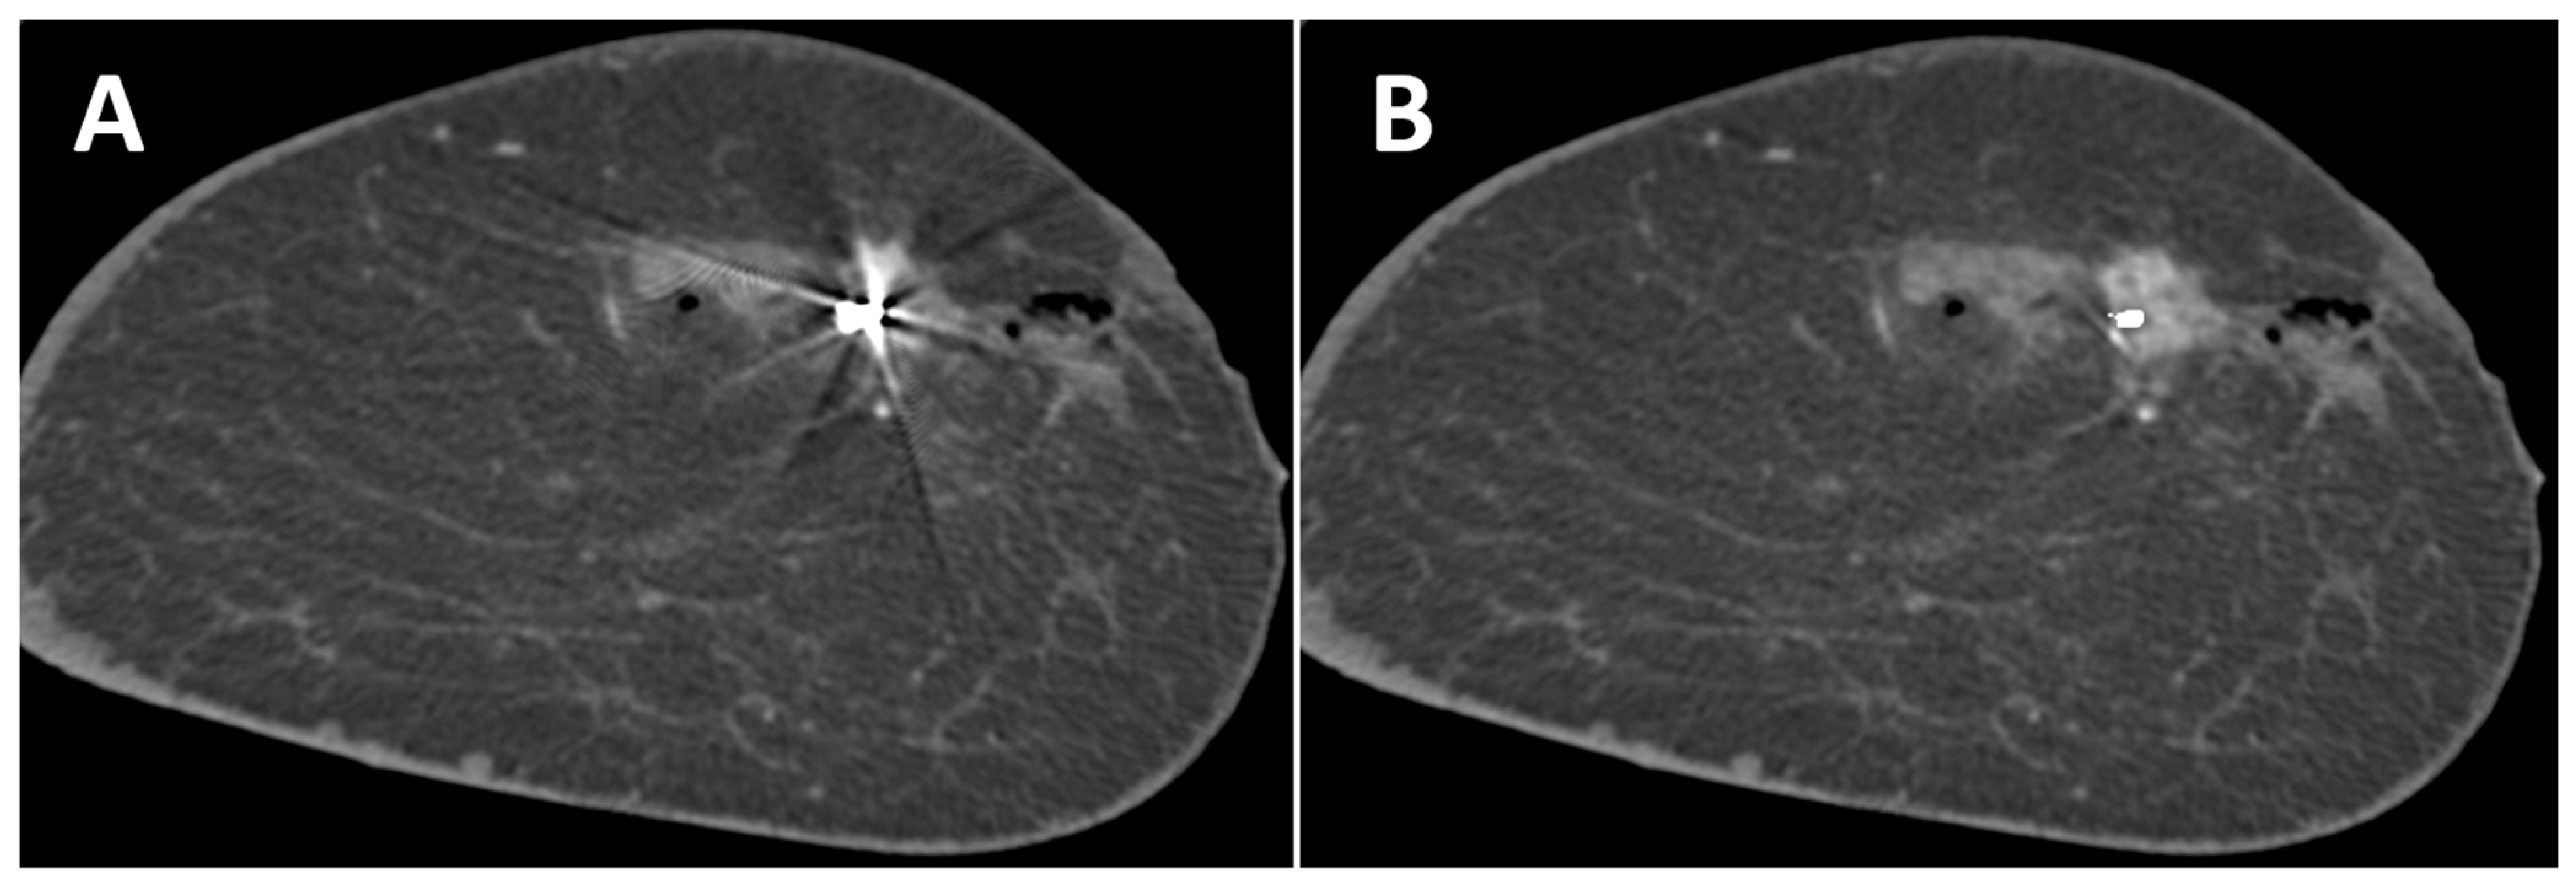

3.2. Effect of MAR on Artifacts

3.3. Effect of MAR on Image Noise and Image Quality

3.4. Detectability of Breast Lesions